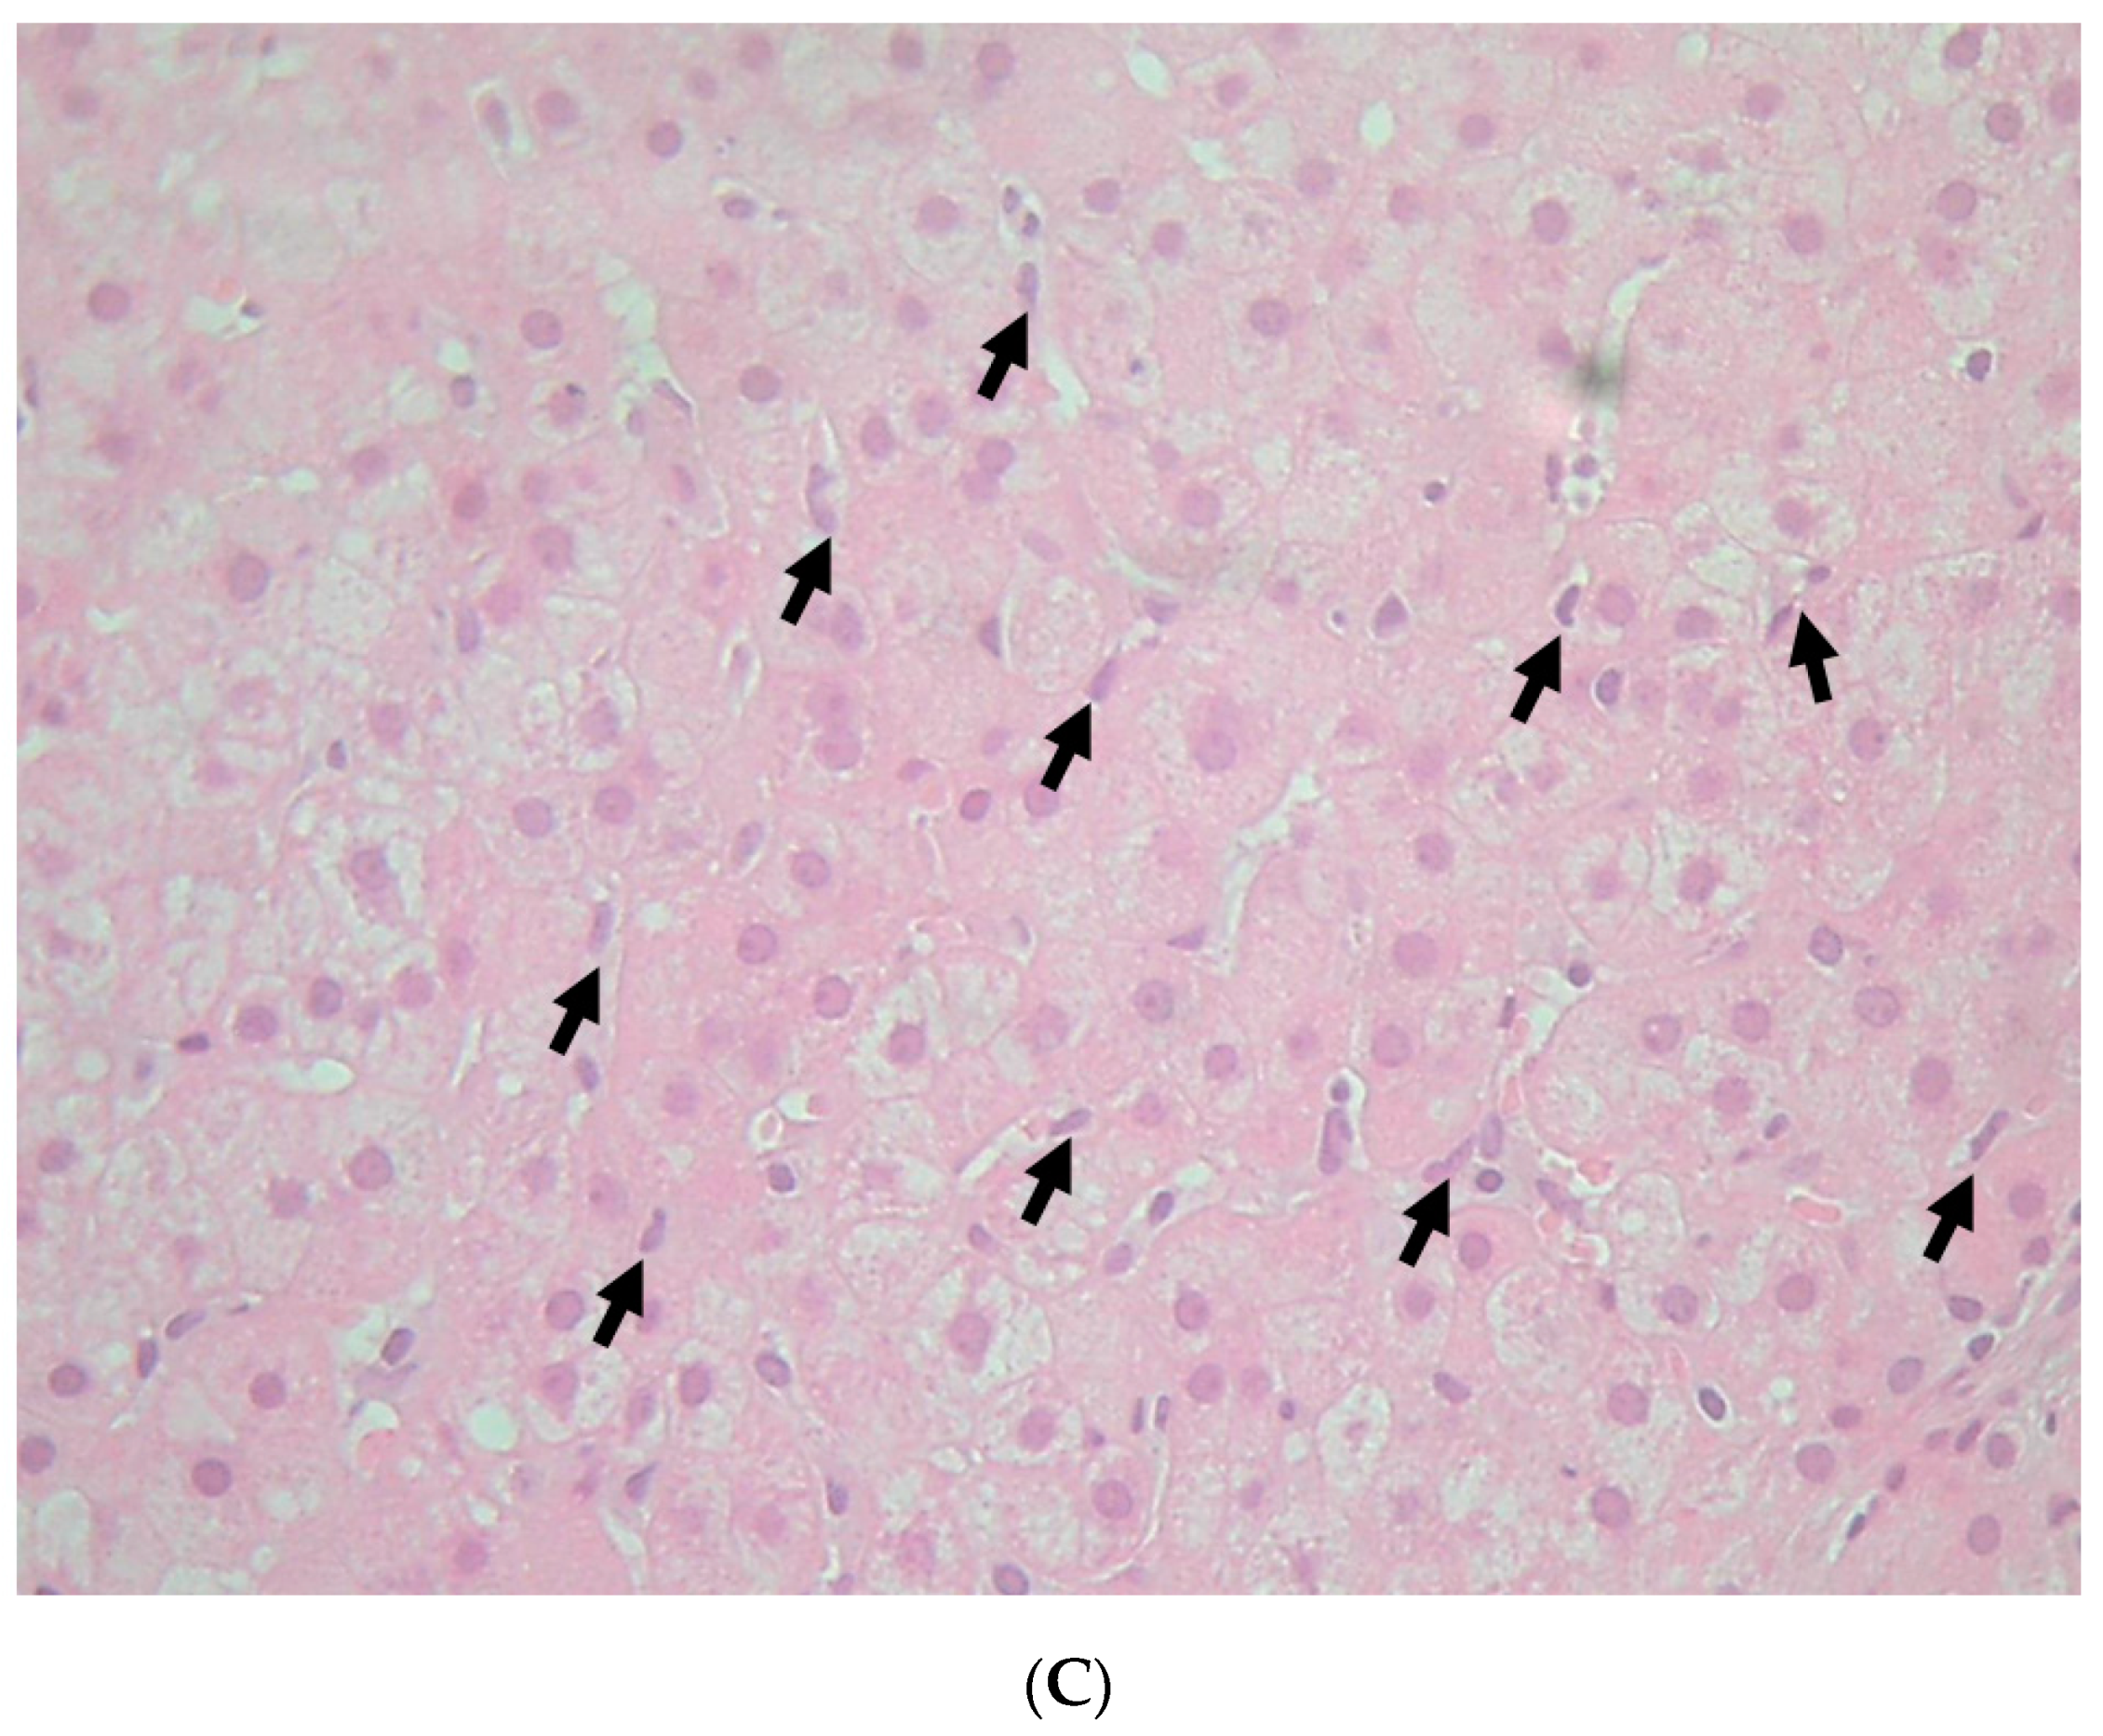

3.4. Pathological Findings and Estimated Theory of FLR Mechanisms